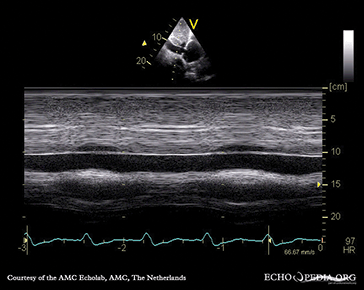

Among leaders in the country to perfect the ability to map and ablate arrhythmias with 3-D intracardiac echocardiography without ionizing radiation